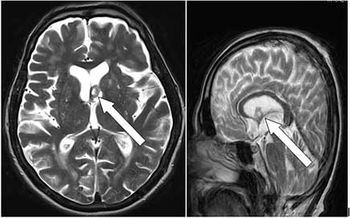

Case History: 75-year-old male with complaint of occasional headaches for last two years.